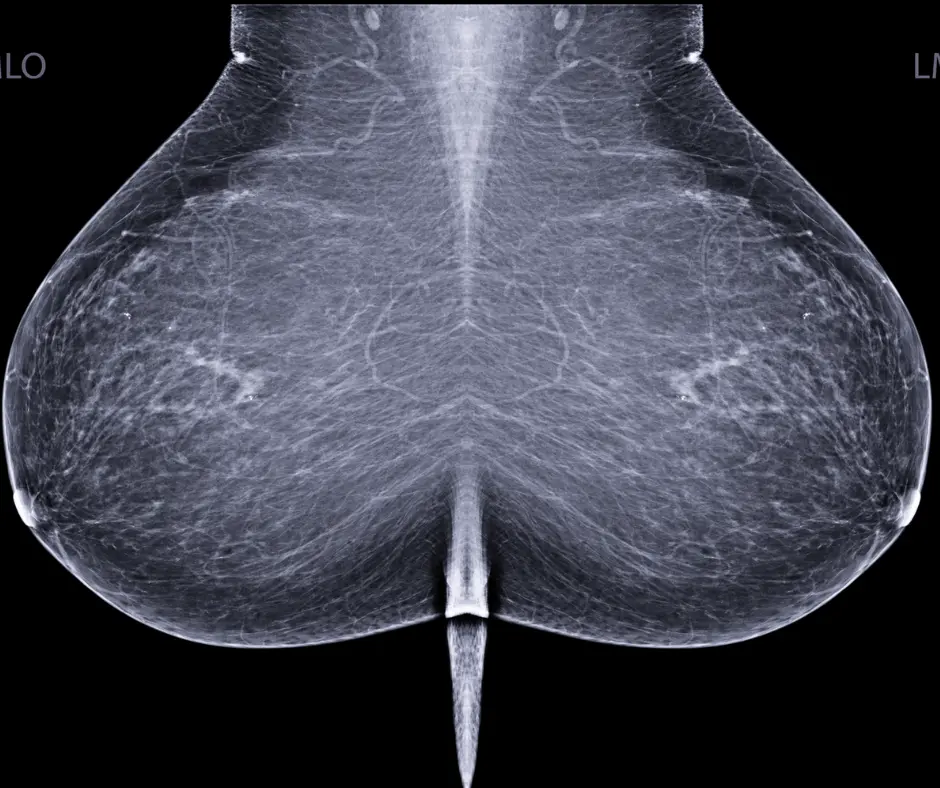

According to the FDA, the proposed amendments to the MQSA specific to breast density notification would require that patient-oriented summaries of mammography reports indicate whether the patient has low- or high-density breasts and include a paragraph about the “significance of breast density.” Additionally, radiologists would be required to identify one of four breast density categories for the patient in the mammography report sent to referring providers, according to the proposed MQSA amendments.

In a recent video interview, Wendie Berg, M.D., Ph.D., FACR, FSBI, a leading researcher on breast imaging, emphasized the urgent need for a national standard on breast density notification to facilitate timely supplemental imaging. She said the news of a final ruling is a welcome development given the high incidence of dense breasts in women and the increased risk for breast cancer.

"I am delighted Rep. DeLauro has a commitment from the FDA to move forward with a national mammography density reporting standard. The 40 percent of women with dense breasts (heterogeneously dense or extremely dense) are at increased risk, about 40 percent of their cancers will be missed on mammography, and they may benefit from adding supplemental screening with ultrasound or MRI,” noted Dr. Berg, a professor of radiology at the University of Pittsburgh.